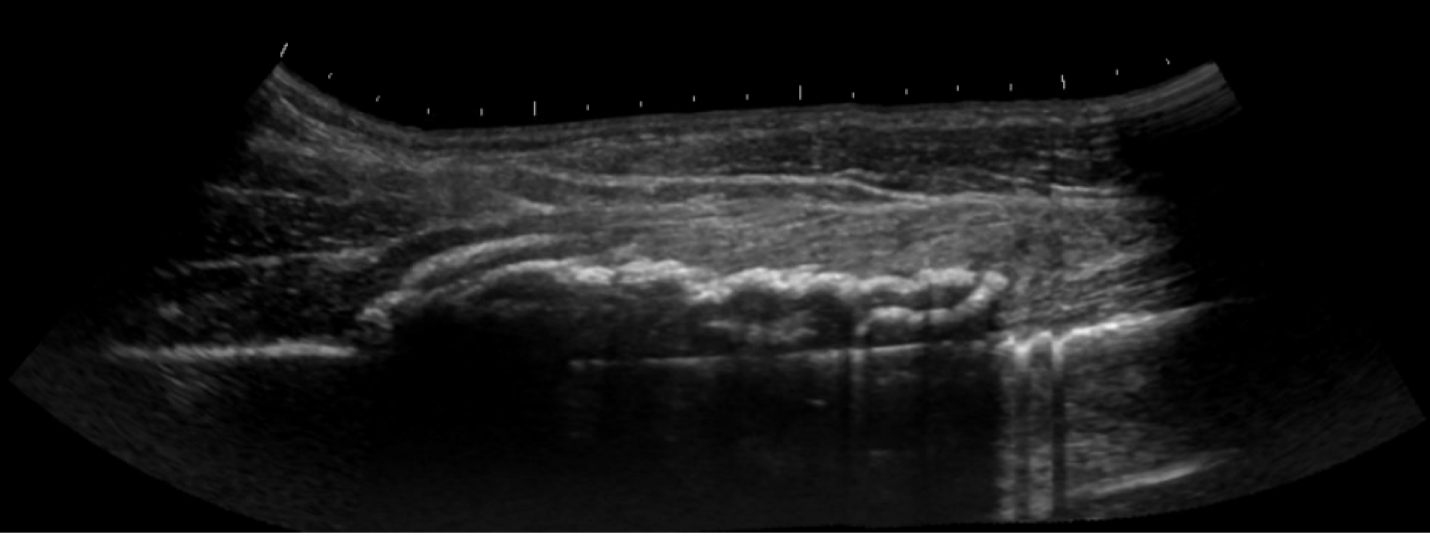

Unlabeled long axis view of the right quadriceps muscle with hematoma two weeks after the initial injury.

Cine short axis evaluation of the quadriceps muscle and myositis ossificans from proximal to distal.